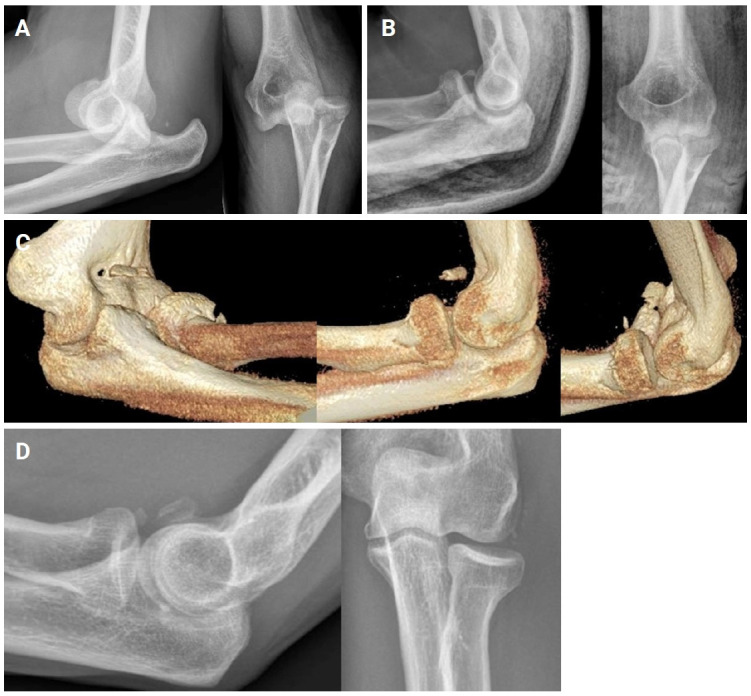

Abstract Image